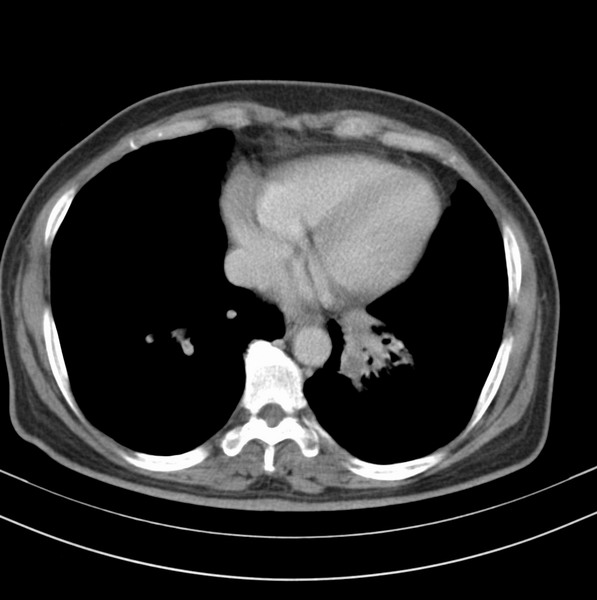

标题: CT20053:胸部增强请会诊。

女、63

咳嗽、胸痛四个月

考虑左下肺中央型肺癌

支持左下中央型肺癌伴阻塞性炎症不张。

包绕左下肺基底段的不规则的软组织肿块,段支气管腔变形、狭窄及阻塞性炎症,病变区不规则强化,又是老年女性支持楼上看法。

典型病例:左下肺基底段中央型肺癌,相应支气管狭窄并阻塞性炎症